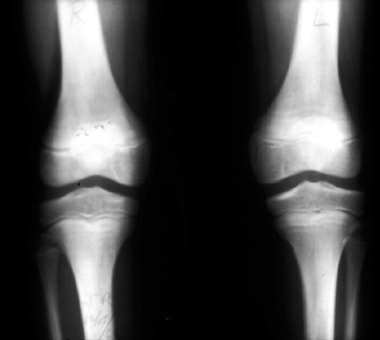

![]() |

Figure 11.8 Langerhans cell histiocytosis of the tibia (A, B) and of the proximal humerus (C) in two children. In both cases, the lesions healed following biopsy, both symptomatically and by radiographic findings.